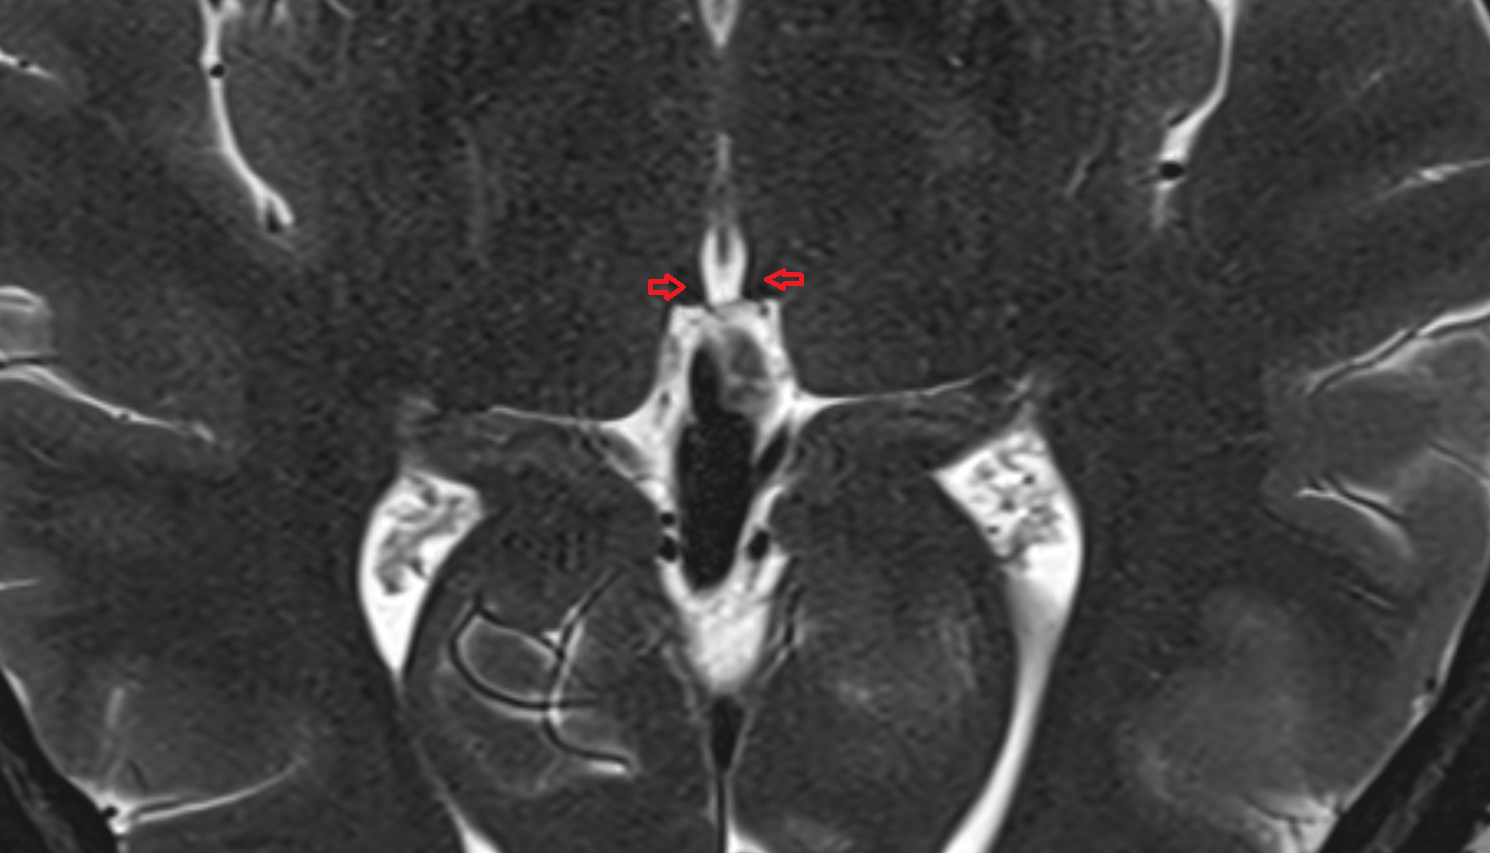

- Meckel’s cave (Trigeminal cave)